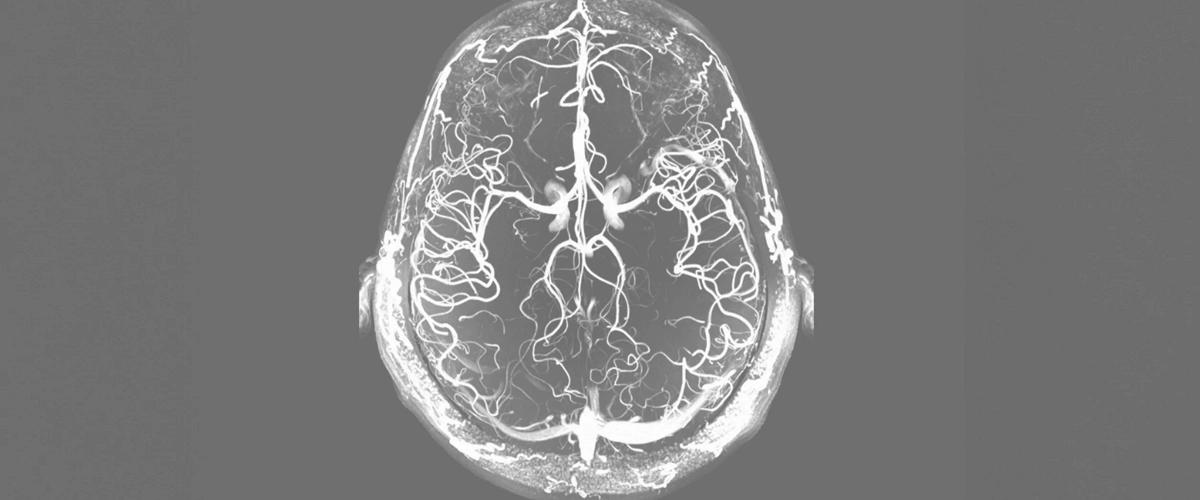

В качестве универсального подхода для терапии и диагностики атеросклероза ученые разработали наночастицы, которые можно вводить в организм неинвазивно, пишет Phys.org. Они могут выявлять бляшки по время визуализации на МРТ, воздействовать на них и доставлять терапевтические агенты.